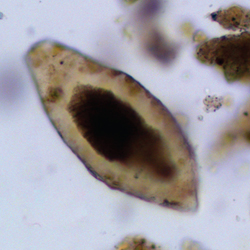

Schistosome egg recovered from the pelvic sediment of a human individual dated between 6,500 and 6000 years ago. Credit: Piers Mitchell

The discovery at Tell Zeidan in Syria shows that the parasite infected humans there at least a thousand years earlier than has been found in Egypt. The oldest schistosomiasis egg found previously was in Egyptian mummies from 5200 years ago. The egg was found in the pelvic area of the burial where the intestines and bladder would have been during life. Control soil samples from the head and foot areas of the grave contained no parasitic eggs, suggesting that the gravesite was not contaminated with the parasite more recently.